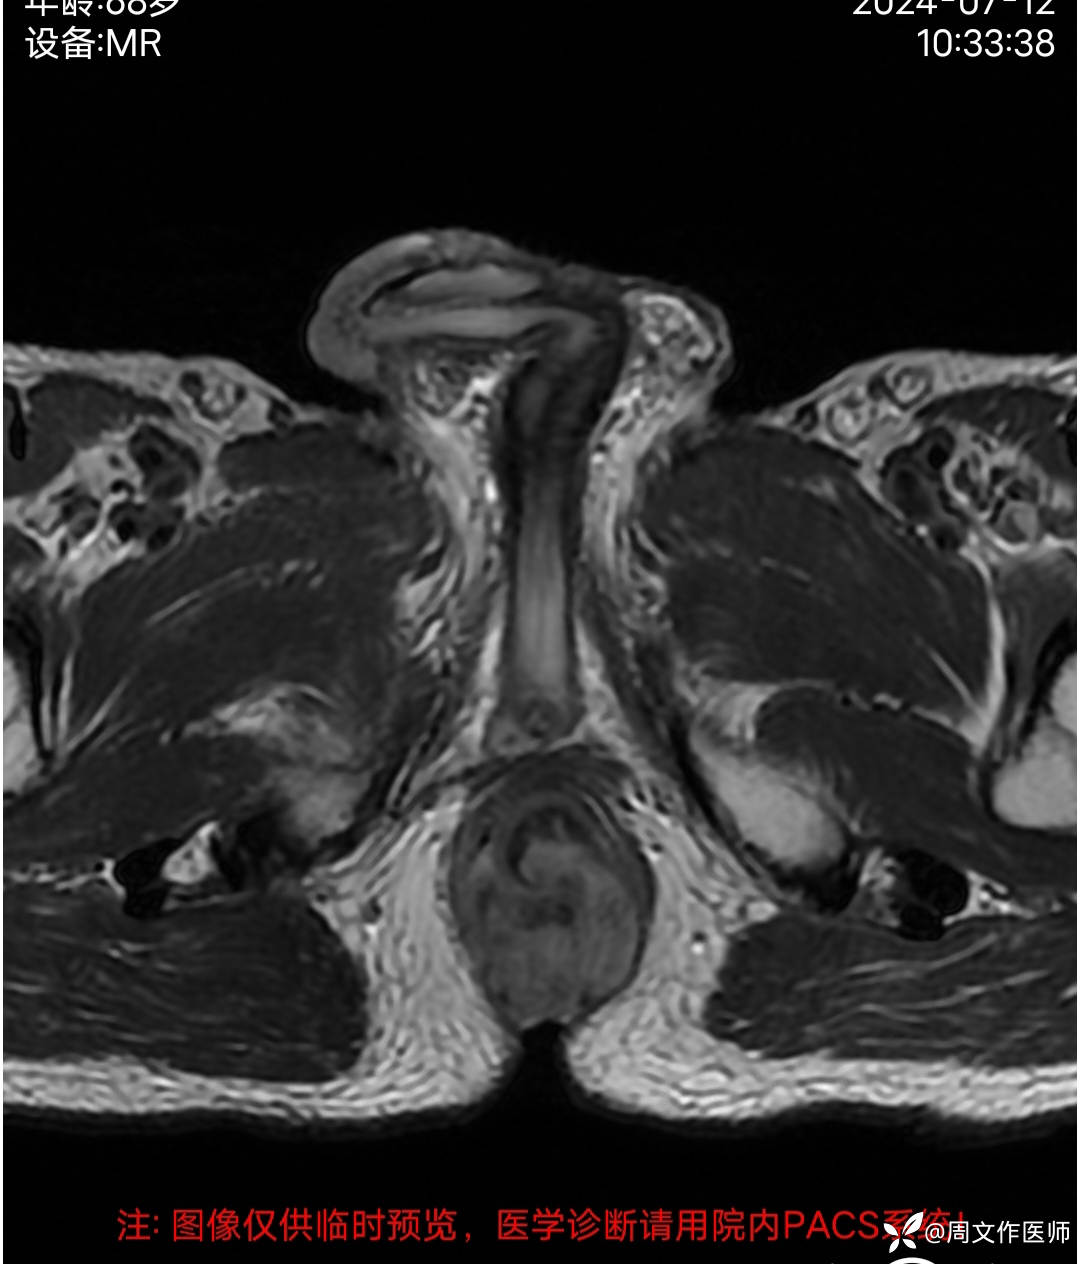

患者男性,68岁,主诉:发现肛门肿物伴出血4年余,加重1月。

现病史:患者诉4年前发现肛门肿物,无疼痛等不适,未引起重视,2年前出现疼痛、出血,脓血溢出至我科住院治疗,完善相关检查确诊直肠癌并发多器官转移至肿瘤科化疗14次,2024年3月因直肠癌肿坏疽穿孔并弥漫性腹膜炎、肠梗阻在外院行 Hartmann手术;病情好转后出院,1月前感肛门肿物逐渐增大,出血及疼痛加重。今日到我院就诊,门诊以"1.肛门肿物;2.便血"收住入院。目前症见:肛门肿物突起,伴疼痛、出血,偶有脓血溢出。病程中患者精神、纳眠稍差,二便正常。体重下降5公斤。

MRI检查